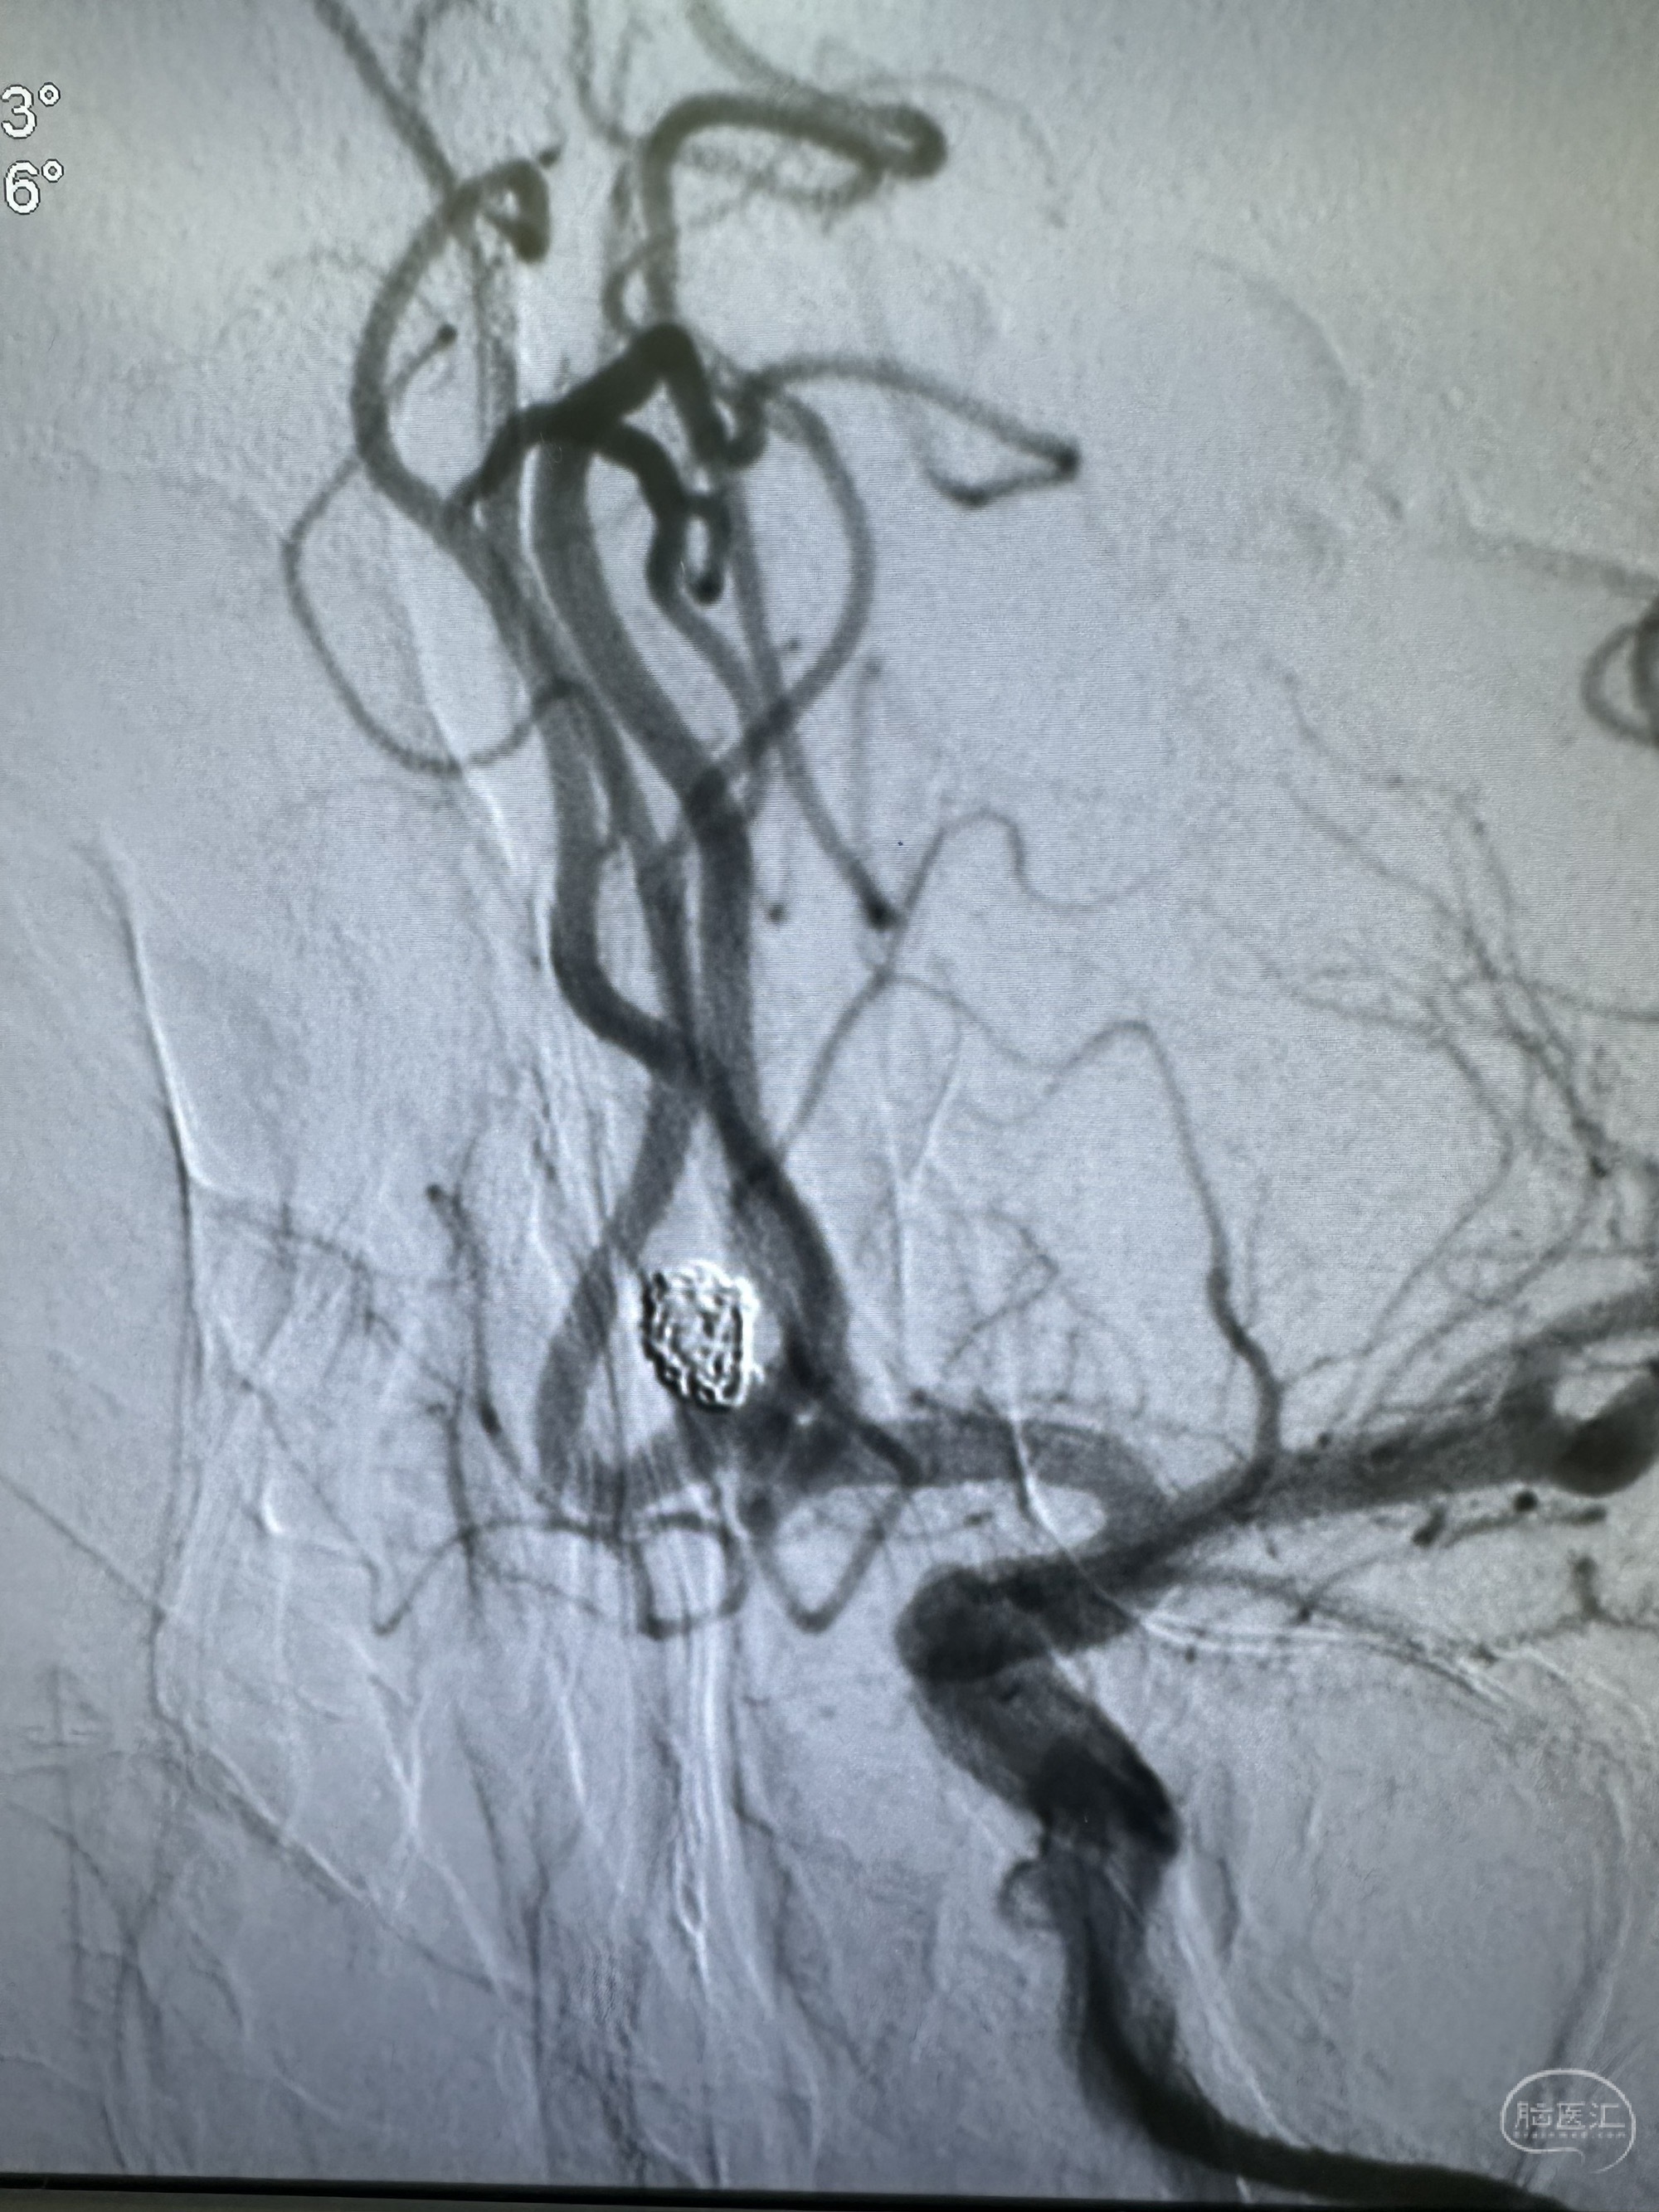

后续填塞三枚ES 3*8,1.5*3,1*3.

最后圈的形态